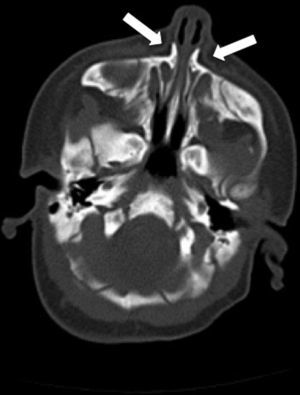

La TAC facial confirmó el diagnóstico de ECAP (diámetro de la apertura piriforme: 8mm; anchura coanal: normal; megaincisivo central y paladar triangular con cresta central (fig. 1).

El diagnóstico se sospecha por la clínica, pero debe ser confirmado por las mediciones realizadas sobre una TAC facial4 (fig. 1).

El hallazgo radiológico más importante es la estrechez del diámetro transversal máximo del orificio piriforme: <11mm2.

Los cortes coronales pueden ser útiles, pero el diagnóstico se basa en los hallazgos de la TC axial.

Otras anomalías radiológicas que se asocian frecuentemente son alteraciones en la dentición (megaincisivo central único) y en la morfología del paladar duro, que se muestra triangular con una cresta en la línea media2.